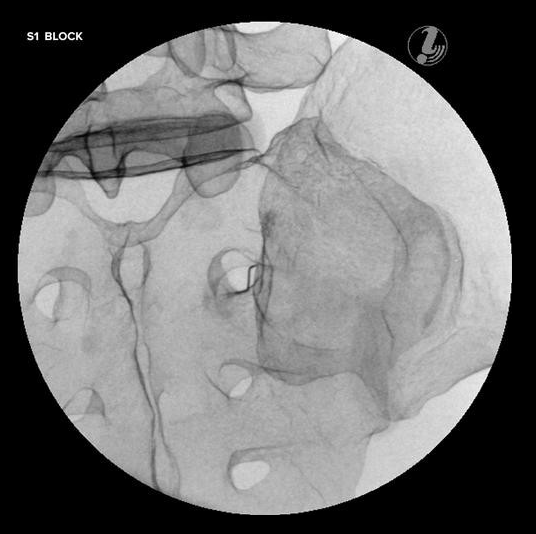

TRENAŻER DO ZNIECZULANIA ZEWNĄTRZOPONOWEGO W ODCINKU LĘDŹWIOWYM POD KONTROLĄ USG

Trenażer do znieczulania zewnątrzoponowego w odcinku lędźwiowym pod kontrolą USG umożliwia naukę diagnozowania źródła bólu, identyfikacji tkanki docelowej i narażonych struktur, przy użyciu USG i anatomicznych punktów.

Przy użyciu symulatora można przeprowadzać m.in:

• blokadę gałęzi podstawnej-przyśrodkowej

• blokadę stawu krzyżowo-biodrowego

Trenażer prezentuje następujące kości:

• kość krzyżową (S1-S3)

• kość biodrową, obustronną bez kości kulszowej i stawu biodrowego

• T12-L5

• kość guziczną.